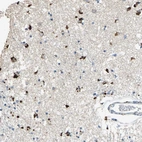

Immunohistochemical staining of human caudate shows strong cytoplasmic positivity in glial cells.